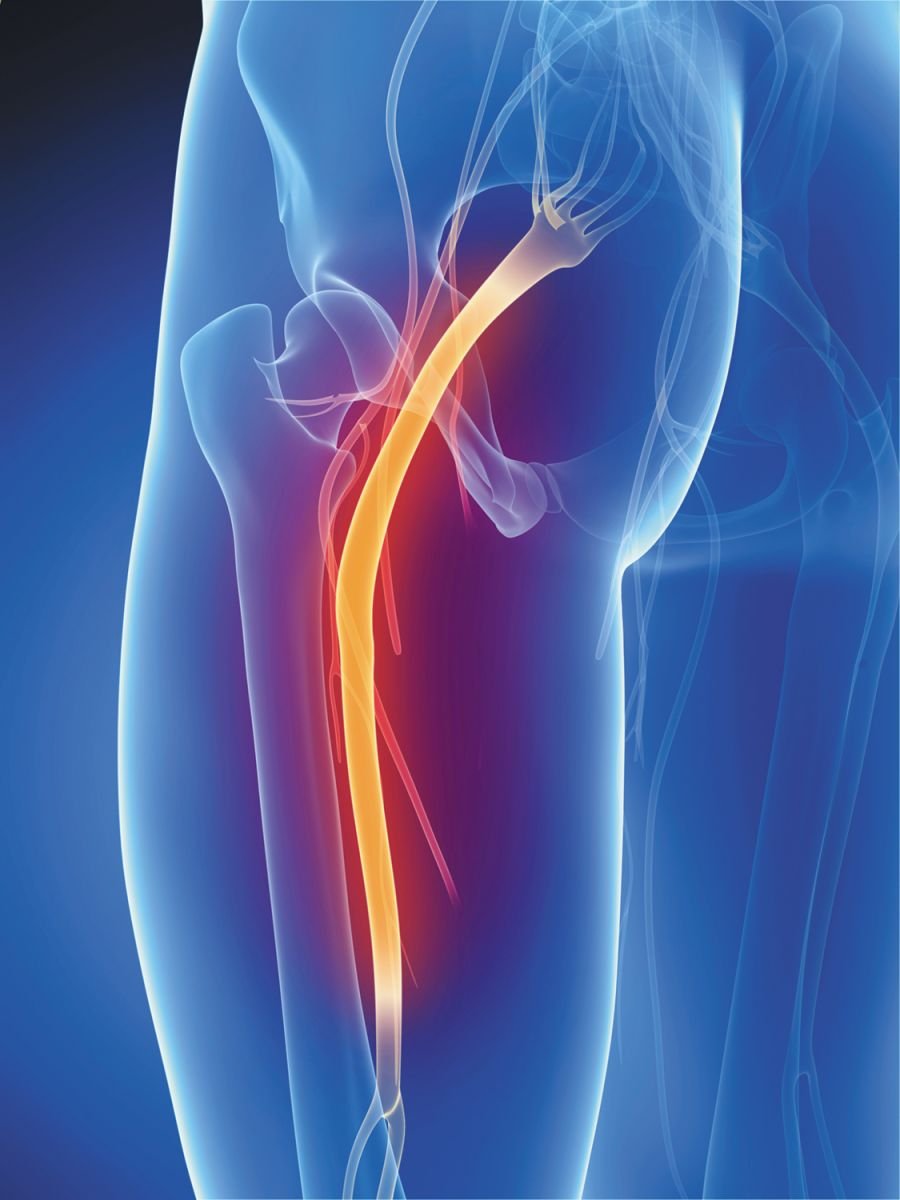

Sciatica